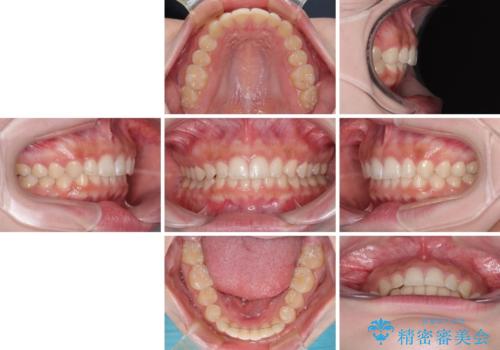

ディープバイトを短期間で改善 ワイヤー矯正治療

左上の歯列は補助装置により速やかに移動し、1年程度で奥歯の咬み合わせが改善され、1年3ヶ月の短期間でしっかりと仕上げることができました。

- 前歯のデコボコとディープバイトを気にして来院された患者様です。

左上前歯前方に飛び出しているため、歯列全体が前方に移動している状態でした。